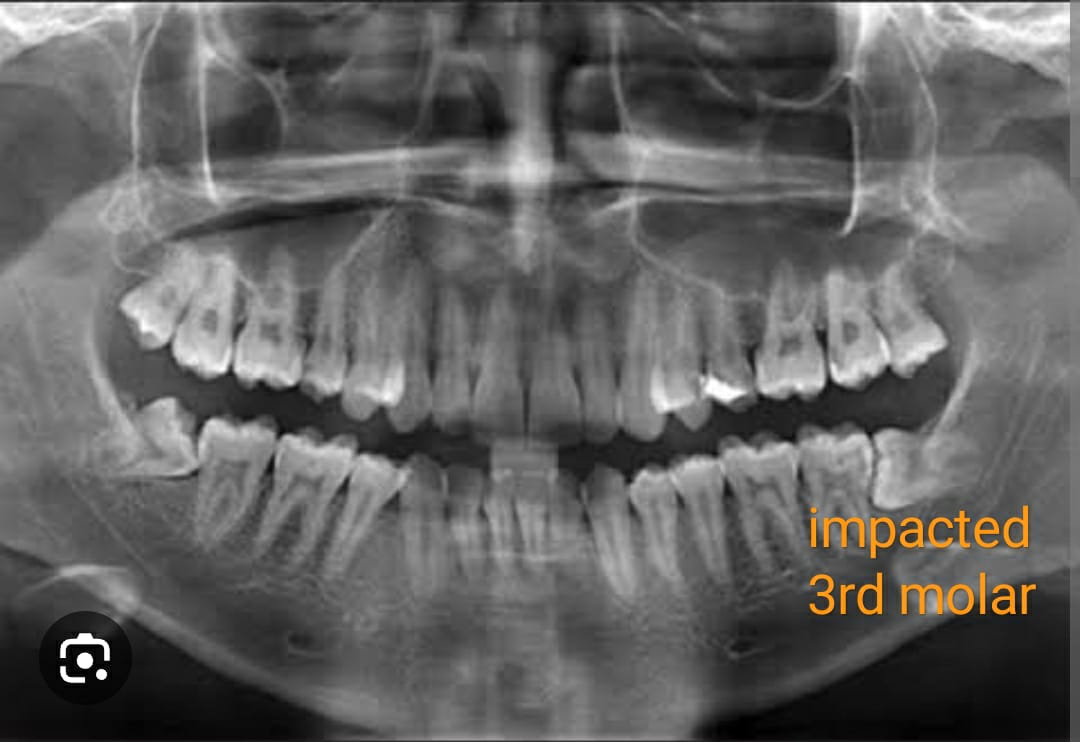

Riya's story is not uncommon. Many young adults face the challenge of wisdom teeth erupting inadequately, causing a host of issues such as pain, infection, and even misalignment of other teeth. The major problem Riya faced was both practical and emotional the persistent dental pain was affecting her quality of life and self-esteem.

Determined to reclaim her smile and her peace of mind, Riya decided to consult with a dental specialist. After a comprehensive examination, it was clear that wisdom teeth extraction was the best course of action. The procedure promised not only to alleviate her pain but also to prevent future dental complications.